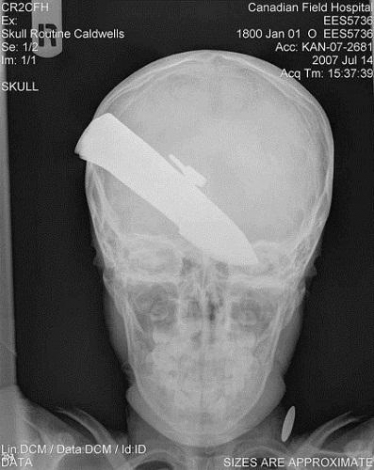

2389482082974153369.jpg

阿富汗赫爾曼德省,一把刀子扎入到一位10歲男孩的頭骨中。